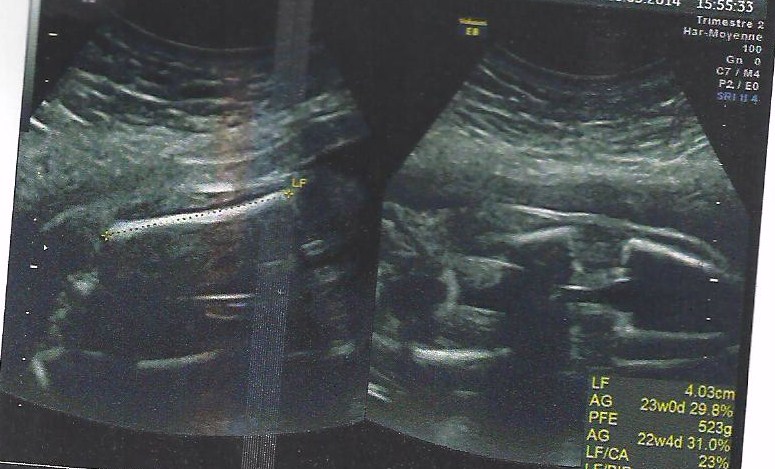

we decided not to find out babys gender until birth , but all guesses are welcome xAttachment 17972